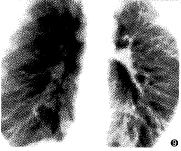

肺动脉造影是确诊PAVMs的可靠方法。肺动脉造影可明确病变部位、形态、累及的范围及 程度,为临床治疗方法的选择提供依据。造影方法分为选择性或超选择性肺动脉造影。一般 先进行选择性主肺动脉造影,正位投照。投照时要包括两肺整个肺野,以免遗漏病变。选择 性主肺动脉造影后,视情况决定超选择性肺动脉造影。笔者通常将导管置于供血动脉进行超 选择性造影,投照时选择适当的角度,如右肺病变选右前斜位(15°~20°)投照,左肺病变 选左前斜位(15°~20°)投照。造影主要表现:单纯型囊状PAVMs可见瘤囊随肺动脉的充盈 显影,引流肺静脉显影早于正常肺静脉,供血动脉及引流静脉均为1支,并见不同程度的迂曲扩张(图2)。较大的瘤囊可见对比剂排空 延迟。复杂型囊状PAVMs可见2支或多支供血动脉及引流静脉,瘤囊内可见分隔,对比剂排空 明显延迟(图4)。弥漫型肺动静脉瘘表现为多发“葡萄串”样小血池充盈,病变部位肺静脉 提前显影(图6、7、9)。

图5~7 X线平片示两下肺斑点状阴影,选择性左下肺动脉及右下肺动 脉造影,示两下肺弥漫型肺小动静脉瘘